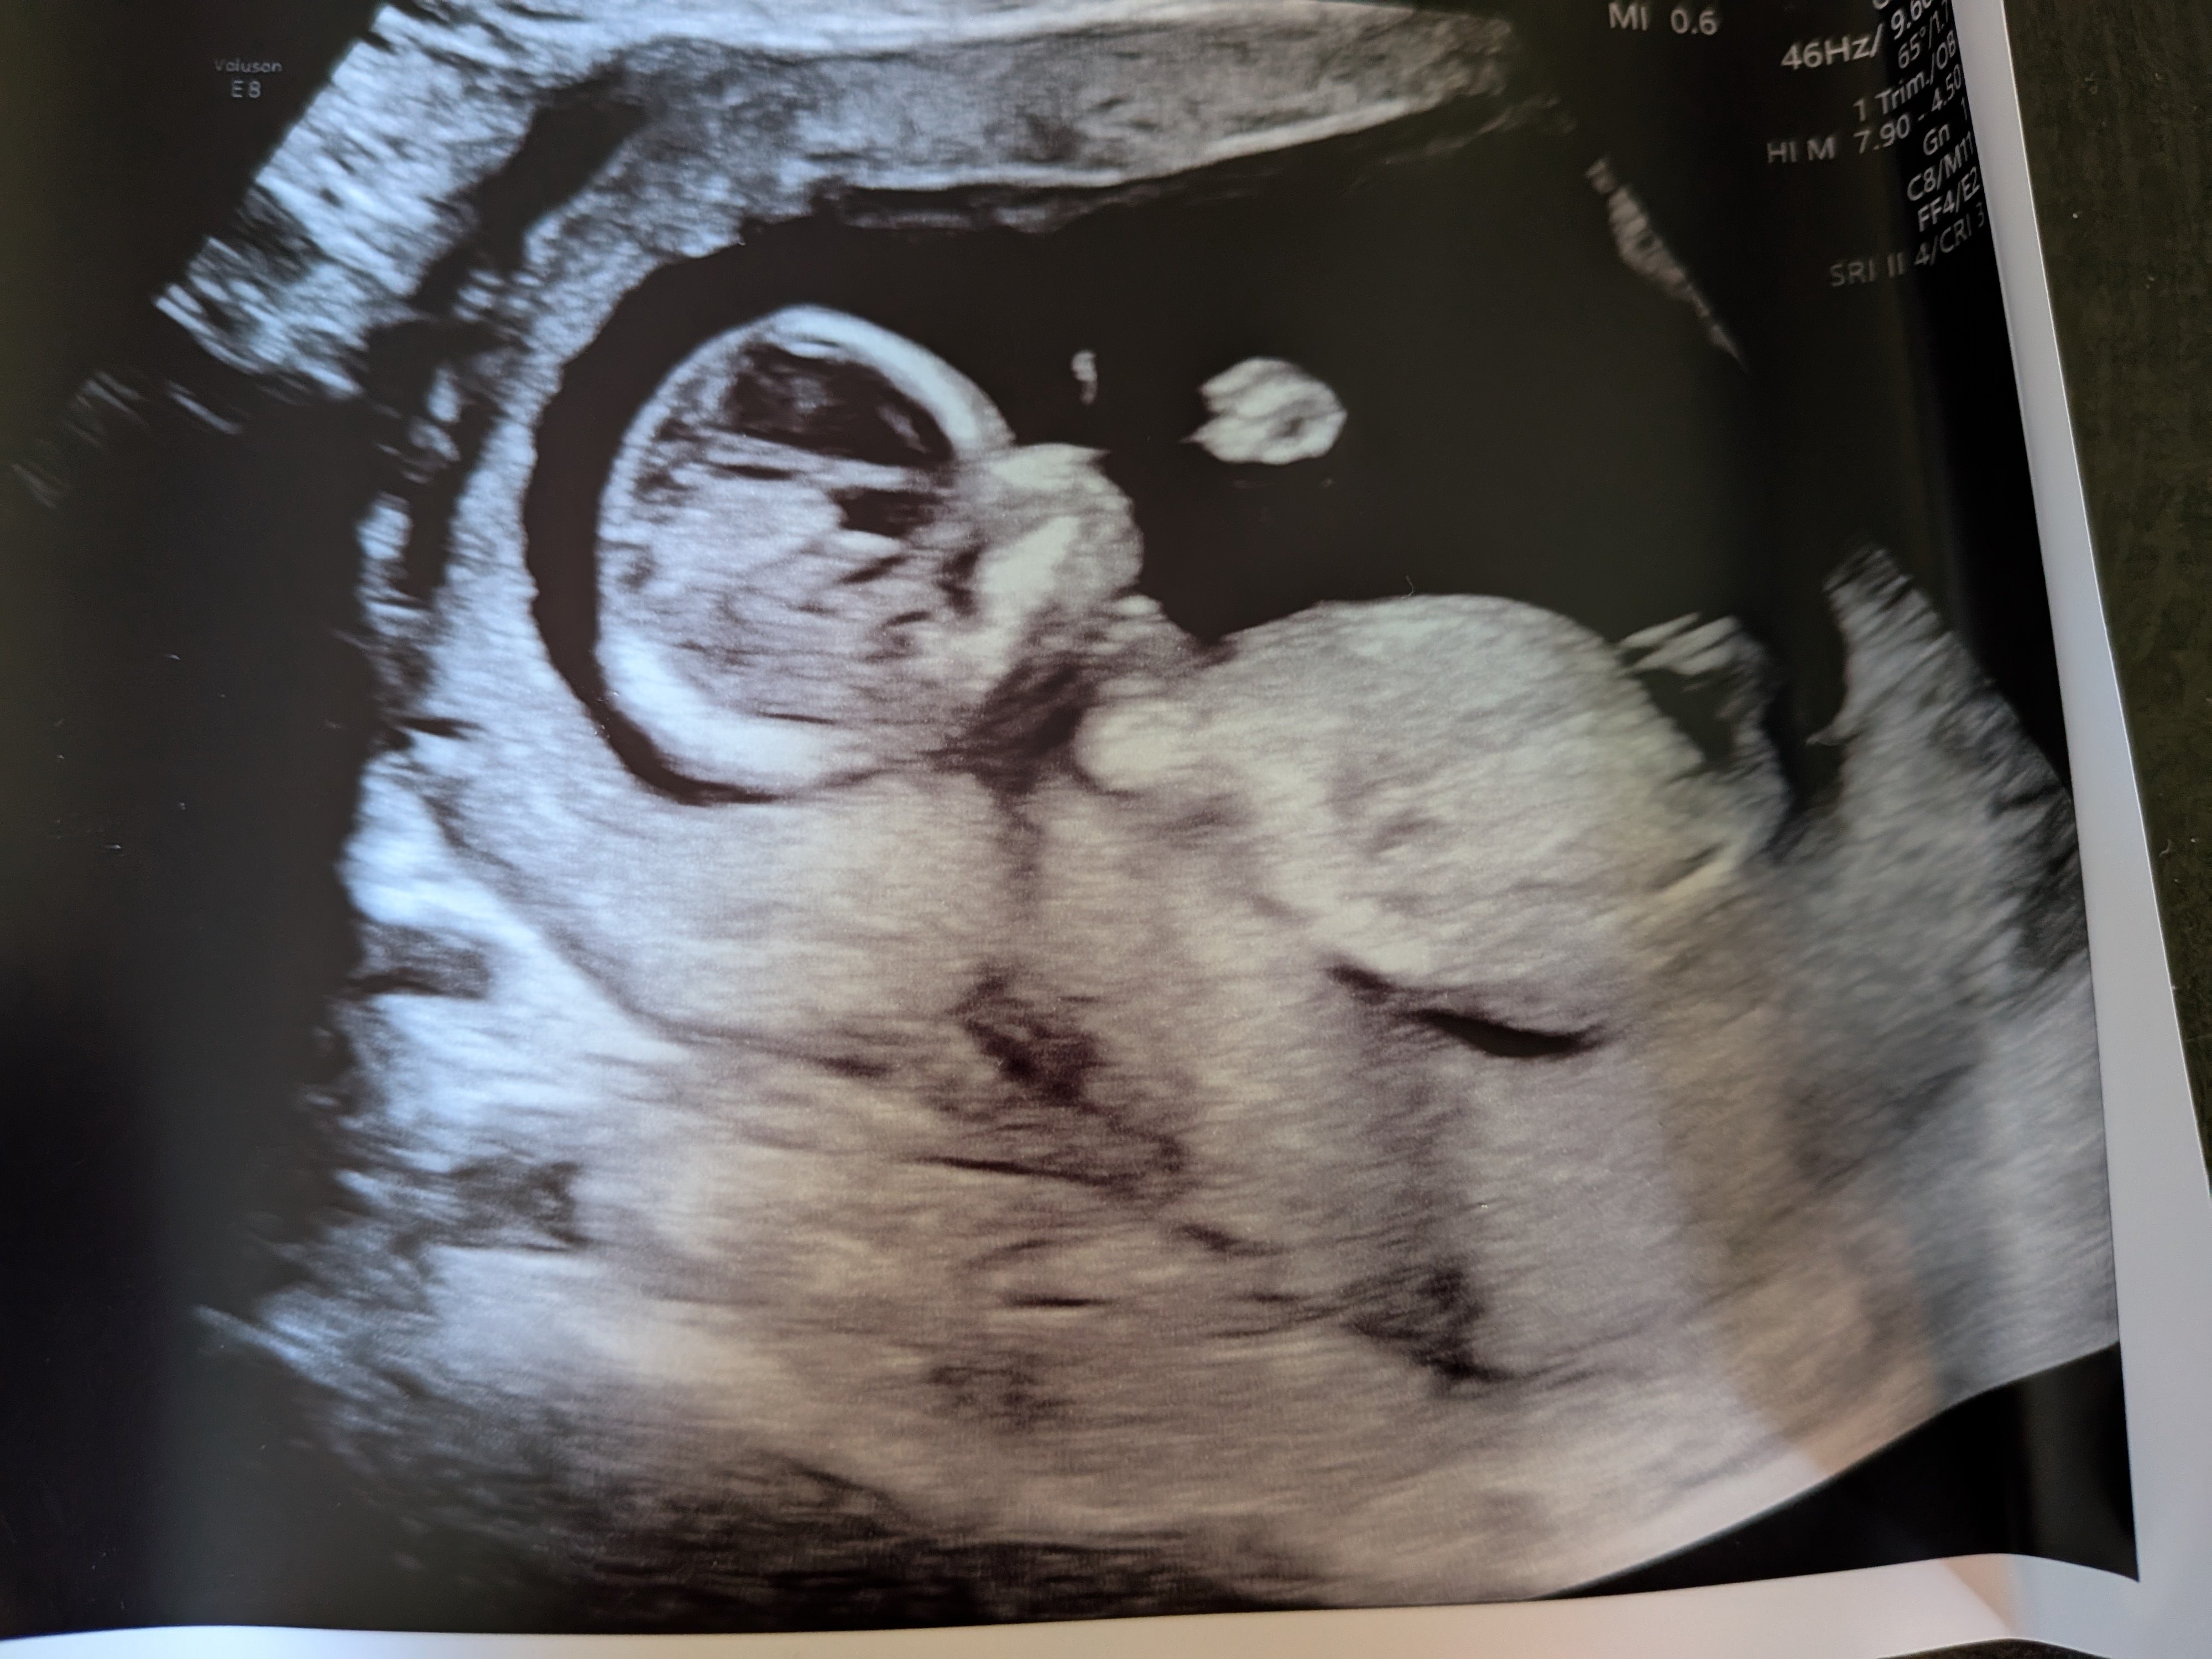

Mannen tenkte feil (selv om han sa kl høyt) og vi endte opp på sykehuset 1 t før OTUL. Utforsket bygget imens. Plutselig fikk jeg sms om at det var min tur! :oops: Viste seg at hun som hadde timen før meg satt fast i kø, så da fikk jeg hennes. Flaks da! Rakk såvidt å bli nervøs. Pratet litt før timen, om forrige fødsel og evt. oppfølging nå, får vite mer om det på OUL. Før vi begynte var hun veldig klar på at man ikke får vite kjønn. Vi sa det går heelt fint, vi er ikke opptatt av det. Jeg syns egentlig folk er litt for opptatt av kjønn :bag: Det syns hun var forfriskende! Også sa hun "eg seie alltid han pga. dialekt". Vi snakket litt videre om datteren vår ila. timen, og etterhvert begynner hun å si "ho" - hun skyldte fort på at det var pga. vi har jente fra før, men lurer på om hun forsnakket seg der :p Anyway, vi så med én gang at det var en frisk og superaktiv krabat inni der! Den hoppet og turnet og snurret rundt - med boksenever foran ansiktet :laughing002 Skulle ikke drukket de slurkene med red bull, for det var vanskelig å få målt :smiley-ashamed004 Men det gikk etterhvert, fikk akkurat nakkefolden til slutt. Ble mange bilder også, inkl. i 3D! Alt så veldig bra ut. Så ingen nub, men jeg kan ikke de greiene uansett. Men basert på at jeg ikke så en penis og en potensiell forsnakkelse lurer jeg på om det blir ei jente til :joyful: Jeg hadde jo egentlig lyst på gutt, men kjenner ikke på noen skuffelse der, selv om det ikke er sikkert ennå. Holder forresten mistanken min privat, for kjente jeg ble litt irritert at alle drev og spurte etter kjønnet etter jeg snappet om vellykket UL :rolleyes: Det er ikke viktig! Senere gikk jeg forbi en Brando Kids og fant ei kasse med ull til 50%, så kjøpte noen plagg i 50-56 :D Det var for det meste "jentefarger" men det driter jeg i :wacky: Fikk btw OUL den 17.09. (18+2)!

Tror kvisene er begynt å bli bedre nå, syns ikke det er like voldsomt, selv om jeg har en del ennå. Utfloden har også minket. Har ikke cravings lenger, bare mer jevnlig sulten. Har kjent litt strekninger i livmor, kjenner meg nesten øm bak ks arret. Vet ikke om jeg kjenner liv, siste uka har jeg kanskje kjent noe som minner om det, men fortsatt usikker. Det kommer nok snart! :happy: Kvalmen er fortsatt relativt mild, så er veldig glad for at 1. trimester har gått så bra! Selv hvis det skulle fortsette til fødsel denne gangen også så går dette nivået fint :hilarious: Trøttheten er litt verre, skulle gjerne hatt litt mer energi, men det kommer nok snart. Jeg ligger på sofaen med god samvittighet, jeg lager et menneske her! :playful: